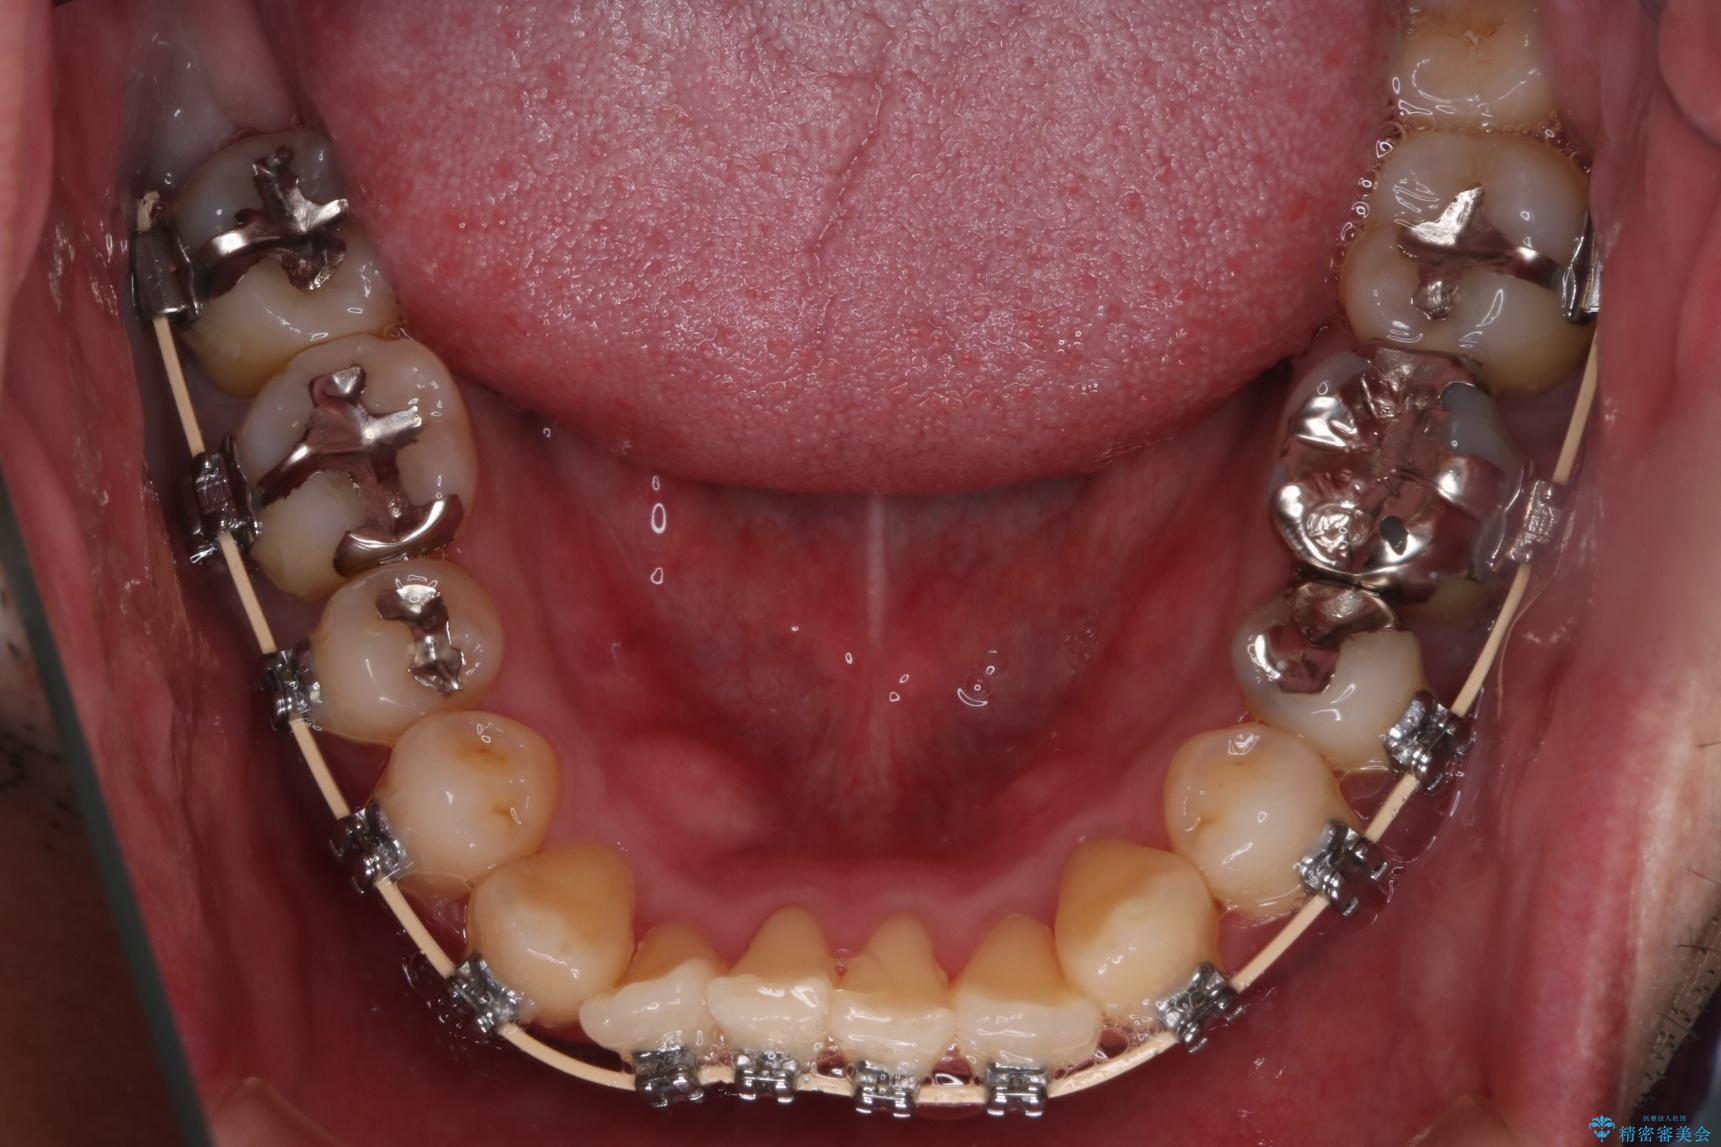

- 矯正装置

- メタル装置

下のがたつきをとるために、IPR(歯と歯の間を削る処置)も行って歯を並べていきます。